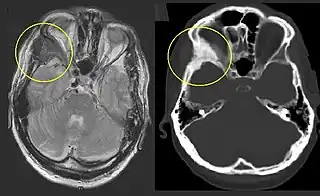

![]() Displasia fibrosa en el hueso cigomático, en comparación con el lado contralateral. | ||

Pueda ayudar evaluar con exactitud la magnitud de la afectación ósea. La intensidad de señal en la resonancia magnética es moderadamente baja en T1, mientras en T2 es alta o media. Con gadolinio, la mayoría de las lesiones muestra un incremento central de contraste y algunos anillos periféricos.[5] En general, la intensidad de la señal depende de la cantidad de trabéculas óseas, colágeno, quistes y hemorragias. El clásico aspecto en la tomografía es de «vidrio esmerilado», que corresponde al hueso sano que rodea a la lesión.[5]